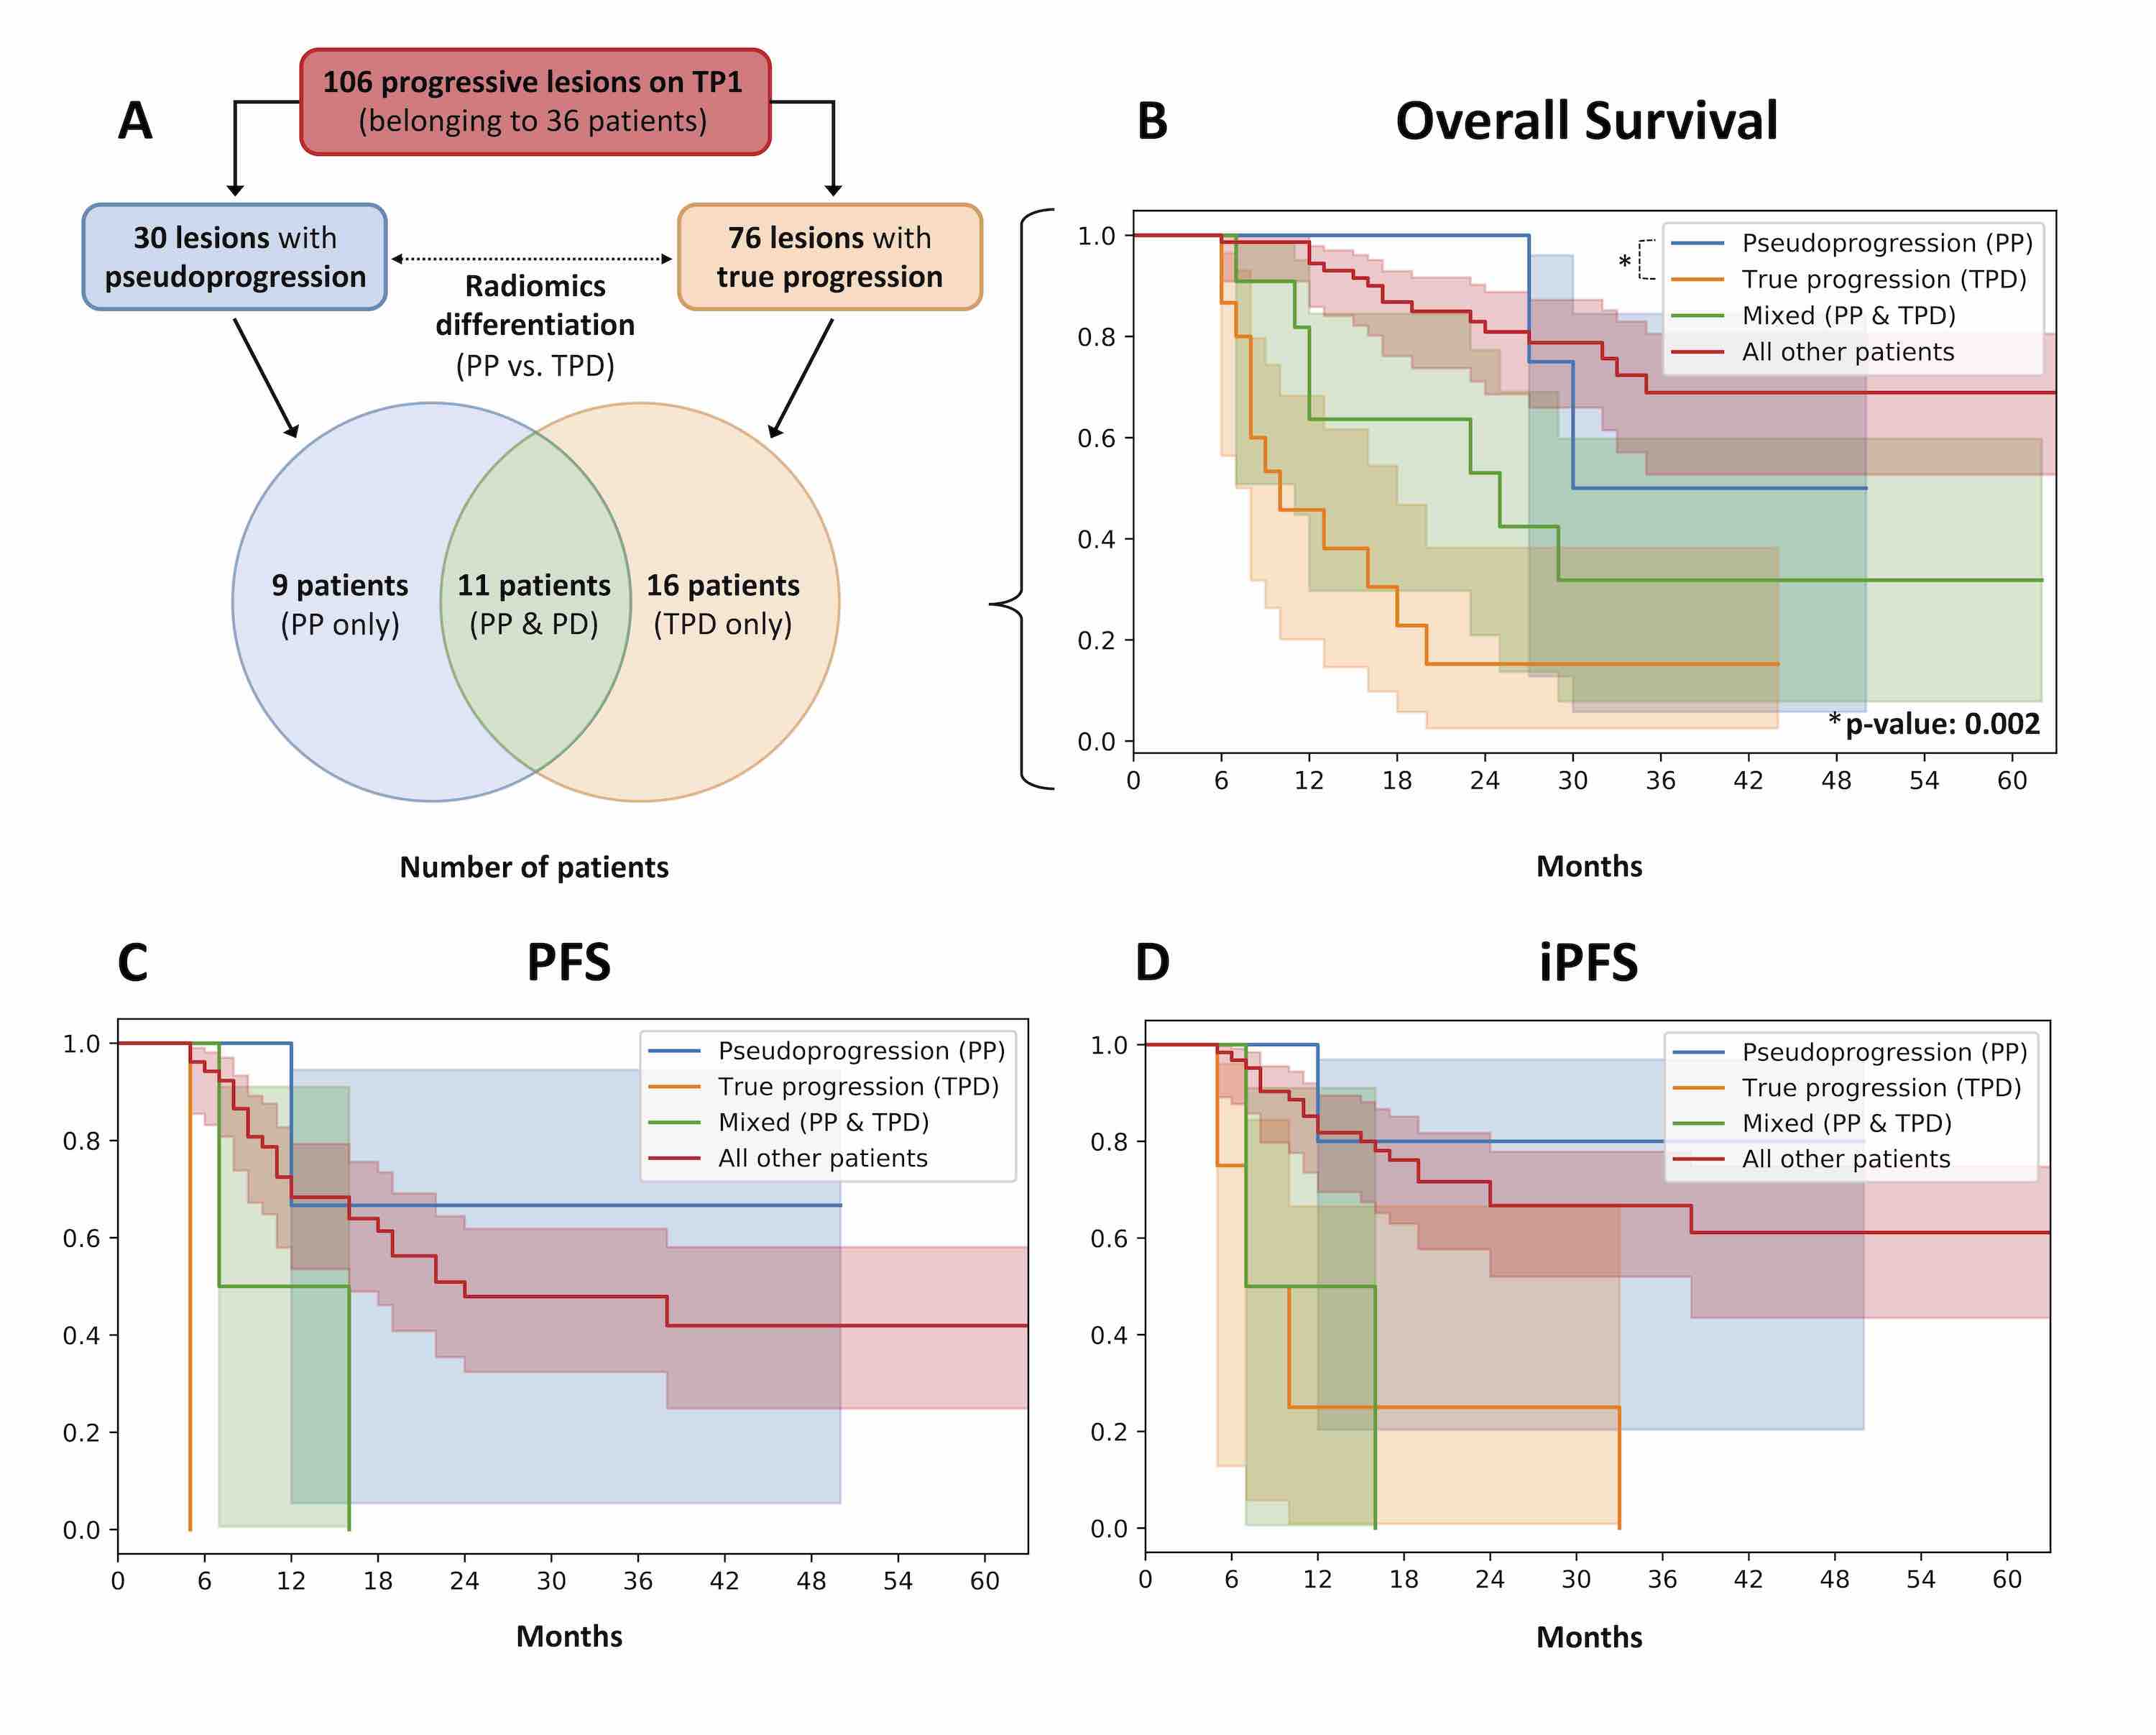

Radiomics, Tumor Volume, and Blood Biomarkers for Early Prediction of Pseudoprogression in Patients with Metastatic Melanoma Treated with Immune Checkpoint Inhibition

Immune checkpoint inhibitors (ICI) have revolutionized the treatment of patients with metastatic melanoma. However, more than 50% of patients do not respond to ICI. ICI response assessment is challenging, as novel response patterns, such as pseudoprogression (PP) are not considered in the response evaluation criteria in solid tumors (RECIST 1.1).

An increase in tumor volume could be based on either true progressive disease (TPD) or on influx of immune-competent cells (PP). Early differentiation of PP and TPD is highly relevant in daily clinical decision-making, and predictive biomarkers are needed for better patient selection. We could identify 2[18F]fluoro-2-deoxy-D-glucose–positron emission tomography/CT-based radiomic and delta-radiomic features as novel imaging markers for early differentiation of PP from TPD. In addition, we could show that the routine blood markers LDH and S100 can contribute to PP prediction.

A multimodality approach of combined radiomics and blood marker–based prediction model at an early time-point of 3 months yielded the best performance. Thereby, added toxicity or delayed treatment switch in patients with metastatic melanoma treated with ICI might be potentially avoided.

PET/CT radiomics for prediction of hyperprogression in metastatic melanoma patients treated with immune checkpoint inhibitors

This study evaluated pretreatment 2[18F]fluoro-2-deoxy-D-glucose (FDG)-PET/CT-based radiomic signatures for prediction of hyperprogression in metastatic melanoma patients treated with immune checkpoint inhibition (ICI).

Fifty-six consecutive metastatic melanoma patients treated with ICI and available imaging were included in the study and 330 metastatic lesions were individually, fully segmented on pre-treatment CT and FDG-PET imaging. Lesion hyperprogression (HPL) was defined as lesion progression according to RECIST 1.1 and doubling of tumor growth rate. Patient hyperprogression (PD-HPD) was defined as progressive disease (PD) according to RECIST 1.1 and presence of at least one HPL. Patient survival was evaluated with Kaplan-Meier curves. Mortality risk of PD-HPD status was assessed by estimation of hazard ratio (HR). Furthermore, we assessed with Fisher test and Mann-Whitney U test if demographic or treatment parameters were different between PD-HPD and the remaining patients. Pre-treatment PET/CT-based radiomic signatures were used to build models predicting HPL at three months after start of treatment. The models were internally validated with nested cross-validation. The performance metric was the area under receiver operating characteristic curve (AUC).

FDG-PET/CT-based radiomic signatures yield potential for pretreatment prediction of lesion hyperprogression, which may contribute to reducing the risk of delayed treatment adaptation in metastatic melanoma patients treated with ICI.